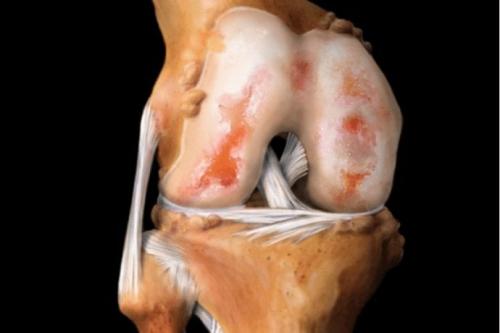

На рисунке показано строение сустава и мы видим, что костные окончания защищены гиалиновым хрящом.

Это своего рода подушка безопасности. Хрящ поглощает силу удара при резких движениях. Как губка, он пропитывается суставной жидкостью. А при увеличении нагрузки на сустав, выделяет ее, чтобы не допустить трения.

Вид на поражённую хрящевую поверхность.